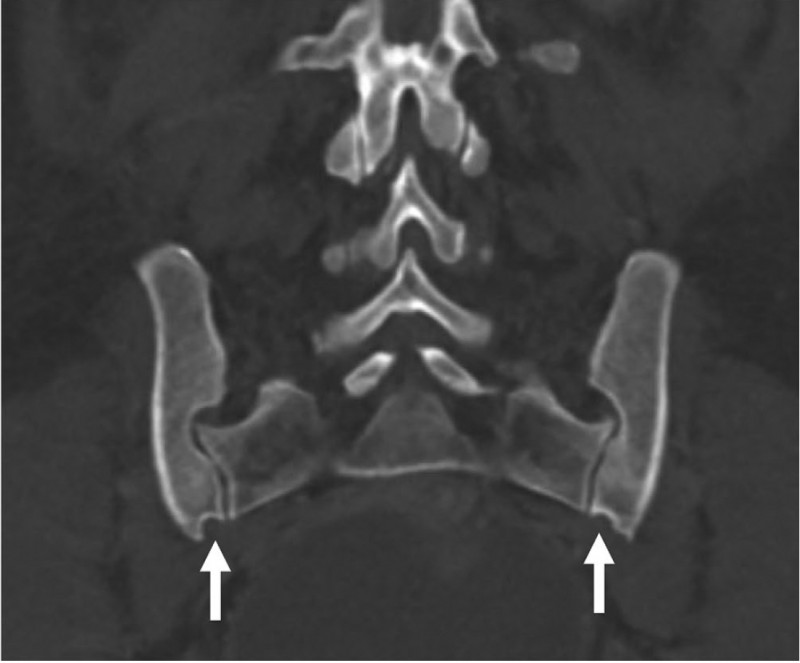

A recent paper in the American Journal of Biological Anthropology, co-authored by KLI group leader Barbara Fischer, challenges the long-held belief that certain pelvic bone features—often called "scars of childbirth"—can reveal a woman's history of pregnancy and birth. Researchers used CT scans to examine the pelvises of women with and without children, as well as men, and found that these bony traits were just as common in women who had never given birth as in those who had. The preauricular sulcus, a groove on the pelvic bone, was found in about half of all women but not in men, suggesting it is linked to sex rather than childbirth. Other features showed no clear connection to pregnancy or delivery. While urinary incontinence was more frequent among women who had given birth, it did not strongly correlate with pelvic bone changes. The study concludes that pelvic skeletal features are unreliable as markers of reproductive history, urging caution in their use for anthropological research.

Catic, A., L.Waltenberger, K. E.Pink, et al. 2026. “Exploring Pelvic Changes: Do Pregnancy and Birth Leave Scars?.” American Journal of Biological Anthropology189, no. 4: e70248. https://doi.org/10.1002/ajpa.70248